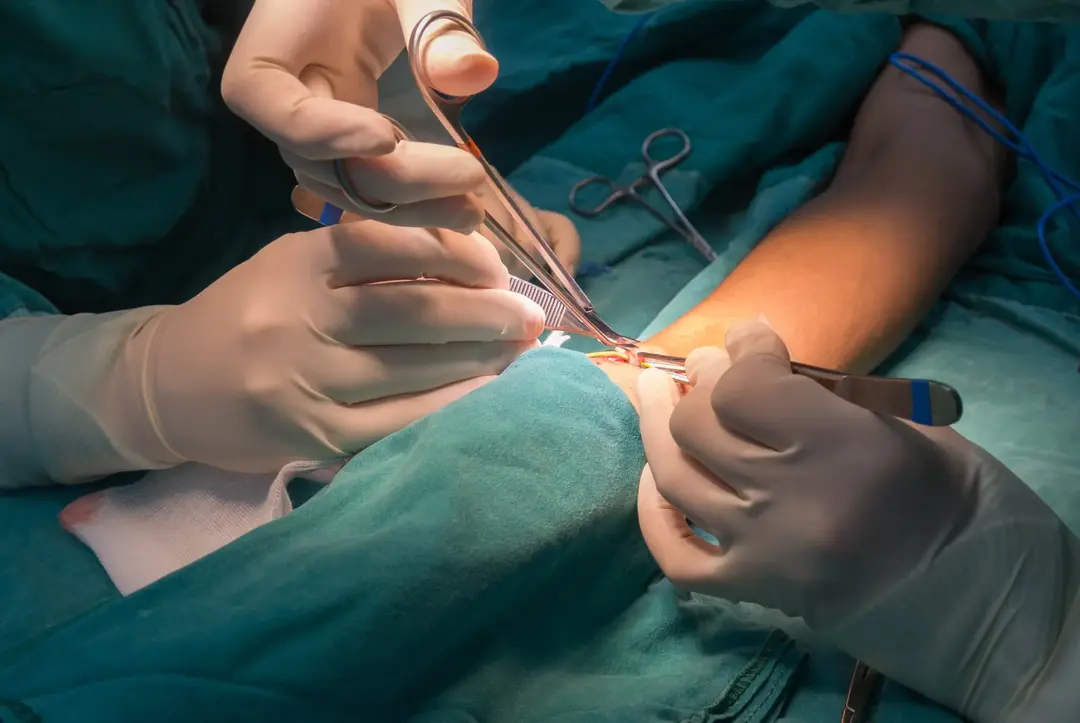

Quando solicitar confecção de FAV no paciente com DRC conservador?

Quando solicitar confecção de FAV no paciente com DRC conservador?